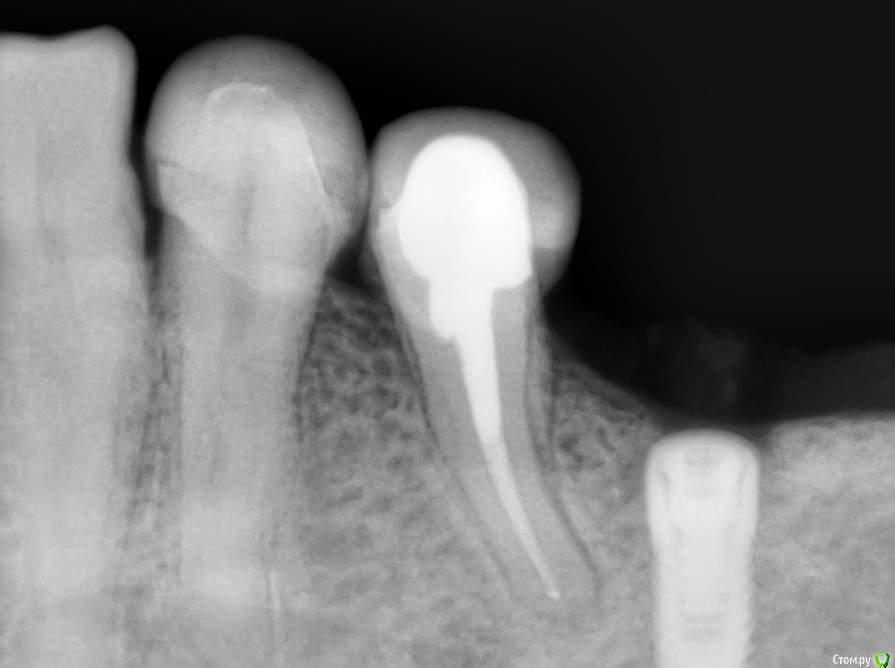

kriokov Опубликовано 7 сентября, 2016 Автор Поделиться Опубликовано 7 сентября, 2016 торк проверю - отпишусь торк 40, все штатно. Открывал без изысков. Крестально разрез, фдм, 2 шва унифлексом. Снимки свежие. 1 Ссылка на комментарий